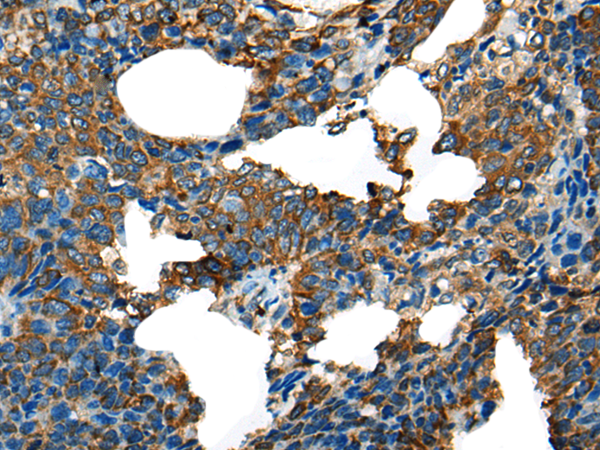

分类: 科研抗体货号: P12855别名: LRPDIT; LRP-DIT应用: IHC反应种属: Human, Mouse